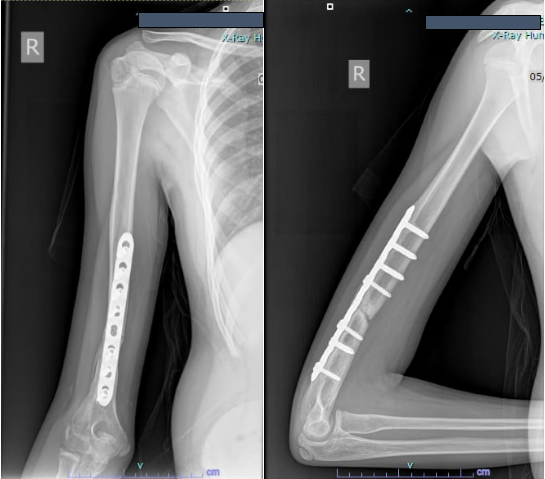

Revision plating with bone grafting was initially considered, but after a multidisciplinary team consultation and with an orthopedic surgeon in Japan experienced in LIPUS, the decision was made to attempt LIPUS therapy.

The procedure was discussed in detail with the parents, as this would be the first reported case in India. After written consent was obtained, therapy was started in February 2020. The treatment area was marked on the skin, and LIPUS was administered daily for 20 min. Monthly radiographs were taken to monitor progress.

By 3 months, early signs of healing were visible. Therapy was continued, and by 6 months the radiographs showed complete union (Fig. 5).

Figure 5: Radiograph at 3 months after starting low-intensity pulsed ultrasound showing early healing.